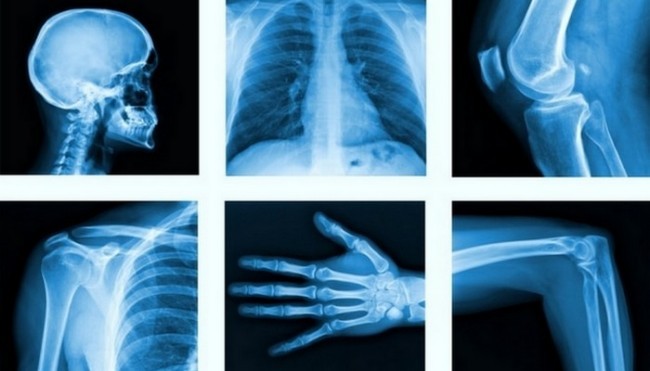

2. Рентген

Бугунги кунда рентген тасвири технологиясисиз суяк синиши каби травмаларга ташхис қўйиш ва тўғри даволашни тасаввур қилиш қийин. Рентген нурланиши немис физиги Вилгелм Конрад Рентген электр токини ўта паст босимдаги газ орқали ўтишини тадқиқ қилинаётган пайтида тасодифан аниқлаган.

Олим барий-платинотсианид билан қопланган электрон-нурли трубка қоронғилаштирилган хонада флуорестсент ёруғлик билан ёритиб турганини сезиб қолди. Катод нурлари кўринмас бўлгани учун у бундай ёруғликни қандай нурлар бераётганини билмас эди ва уларни рентген нурлари деб атай қолди. Олим ўз ихтироси учун 1901 йилда тарихда илк бор физика фанидан Нобел мукофотини олишга сазовор бўлди.